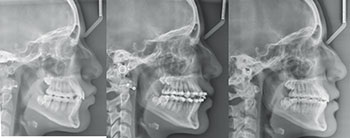

The second case is a 17-year-old male. Despite the crowding and protrusion, I felt that non-extraction treatment had a reasonably good chance of success. I initially flipped his upper incisor brackets in anticipation of needing negative torque. However, the progress records from the pan/repo/ceph appointment at seven months revealed to me that continuing with the non-extraction plan in my hands was not prudent. I did not feel confident that, even with the prospect of safely pushing the limits of IPR and negative torque, I would be able to position his upper incisors in an ideal AP and labiolingual position. The decision was made at that appointment to un-flip (reposition) the upper incisor brackets and refer for the extraction of his upper first bicuspids and lower second bicuspids. The treatment was completed in 25 months, resulting in a favorable position of his upper incisors within his face and smile.